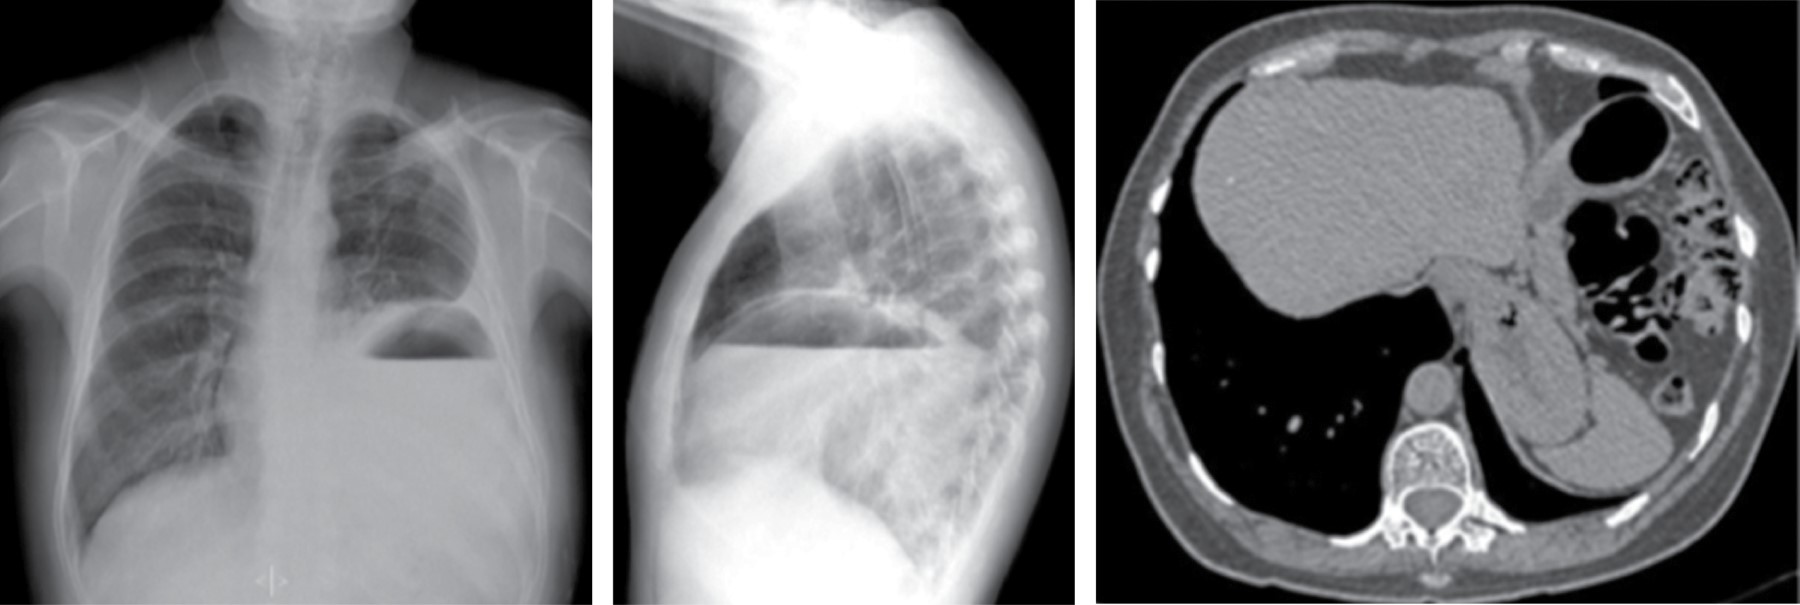

Los hallazgos tomográficos incluyen colecciones líquidas, gas en el mediastino, incremento en la atenuación de la grasa mediastinal, ensanchamiento mediastinal, derrame pleural, derrame pericárdico y presencia de linfadenopatía, en asociación con anormalidades periesternales tales como edema de tejidos blandos, separación esternal con resorción ósea marginal, esclerosis y osteomielitis (Figura 2). Los primeros dos hallazgos son caracterizados en la literatura como altamente positivos.7

Las hernias hiatales por deslizamiento están comúnmente asociadas con un incremento aparente en la grasa mediastinal que rodea el esófago distal secundaria a la herniación del omento, a través del ligamento frénico-esofágico. Radiológicamente, la presencia de una masa mediastinal con nivel hidroaéreo en su interior (Figura 7), permite el diagnóstico certero de hernia hiatal, puede extenderse a la derecha, izquierda o bilateralmente, desplaza el receso acigoesofágico. Los hallazgos tomográficos con un hiato esofágico ancho, visualización directa de contenido abdominal, identificación de la unión esófago gástrica, pueden asociarse a atelectasia, consolidación por microaspiración de contenido gástrico.